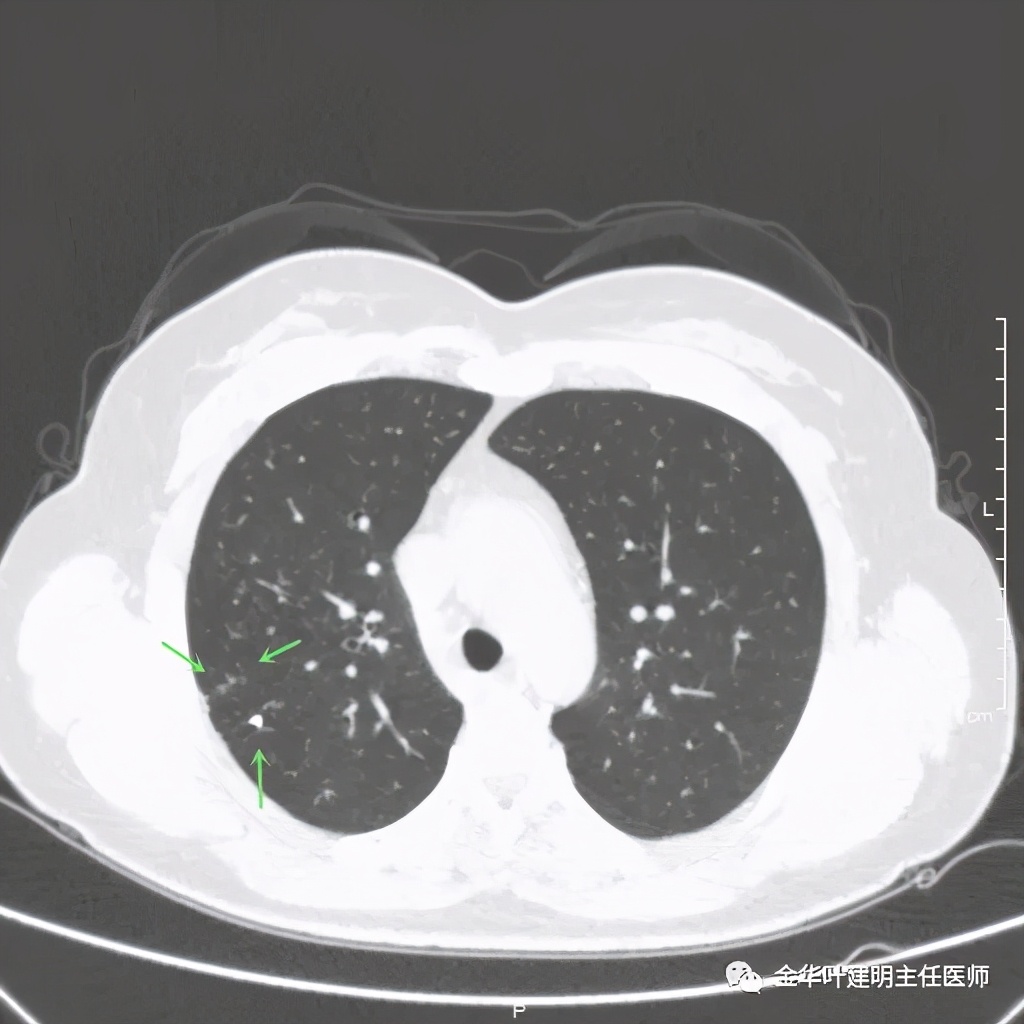

距主病灶一段距离的地方,也有小的实性微结节

总体感觉病灶较大,但边缘过于光滑,缺乏收缩力,没有毛刺征、分叶征、胸膜凹陷征;旁边却有多发微小实性或似磨玻璃结节,周围不清爽。让人感觉非肿瘤性质,炎性可能性大些,比如结核等。那么纵隔窗又是如何呢?我们选两个层面来看: